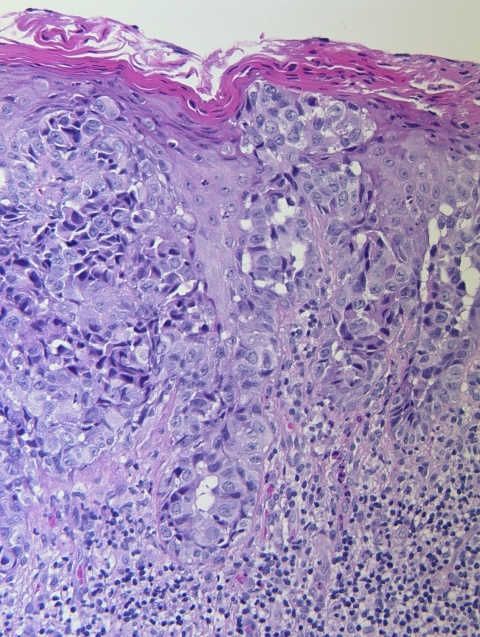

Dermatologie